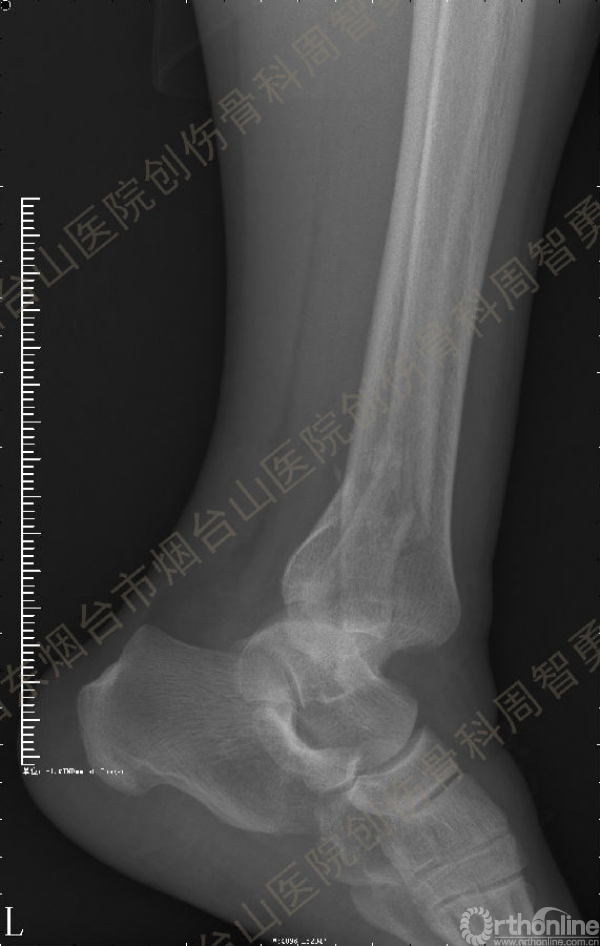

患者一般情况可,左踝关节肿胀,见皮下瘀斑,内、外、后侧有压痛,左踝关节主动运动受限,左足皮肤感觉、血供未见明显异常,左足趾各关节可主动运动。左踝关节正位X线片和CT重建示内踝内上方双层骨皮质影(图1a,c),CT示后侧骨折块分为后内侧骨折块和后外侧骨折块(图2a,b),后内侧骨折块累及内踝后丘,后丘骨折线呈冠状位(图2c),后内侧骨折块腹侧有向近端塌陷的小块骨软骨骨折块(图2d),CT也显示Chaput骨折块(图1c,2e)。

经典的后踝骨折发生于低能量旋转外力所致的踝关节骨折;标准pilon骨折见于高能量轴向暴力;而后侧pilon骨折是旋转外力和轴向暴力共同作用的结果,属于中等能量的损伤。踝关节骨折中的后踝骨折源自下胫腓后韧带的牵拉,骨折块位于后外侧,常为单一的三角形骨折块,大小从关节外片状骨折到累及胫骨远端关节面矢状径的40%(图4a)。后侧pilon骨折中的后侧骨折块较大,累及内踝后丘(三角韧带深层起点)在内的整个胫骨远端后侧,分为后内侧骨折块和后外侧骨折块,后内侧骨折块腹侧有向近端塌陷的骨软骨骨折块(图4b)。后侧pilon骨折中的内踝骨折线并不是水平位而是冠状位,可合并内踝前丘骨折。后侧pilon骨折踝关节正位X线片示特异性的内踝内上方双层骨皮质影(图1a,c)。这是由于后内侧骨折块的骨折线延伸到胫骨远端骨骺和干骺端的内侧骨皮质,其移位后的边缘成像所致。水平位CT显示后侧骨折块分为后内侧骨折块和后外侧骨折块,矢状位CT示后内侧骨折块腹侧有向近端塌陷的骨软骨骨折块。

↑ 图 2a

↑ 图 2b

↑ 图 2c

↑ 图 2d

↑ 图 2e

图 2 术前CT,显示后侧骨折块分为后内侧骨折块和后外侧骨折块(a,b),后内侧骨折块累及内踝后丘,后丘骨折线呈冠状位(c),箭头所示后内侧骨折块腹侧有向近端塌陷的小块骨软骨骨折块(d),Chaput骨折块(e)